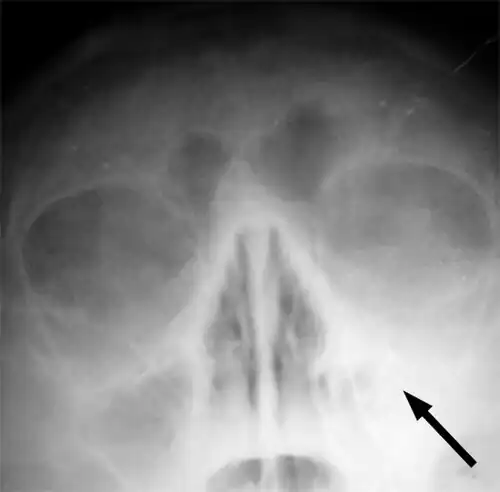

Maxillary sinusitis caused by a dental infection associated with periorbital cellulitis -

Frontal sinusitis -

X-ray of left-sided maxillary sinusitis marked by an arrow. There is a lack of air transparency, indicating fluid in contrast to the other side.